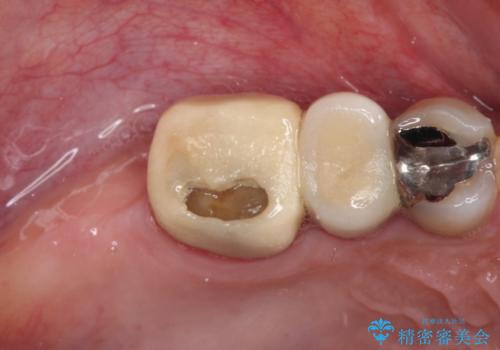

- 奥歯を治療しようと他院で開始したものの、放置してしまったとのことで来院された患者様です。

外れてしまった銀歯や穴の空いた仮歯などあり、適合の悪い被せものと合わせて、セラミッククラウンやセラミックインレーにて治療と行うこととしました。